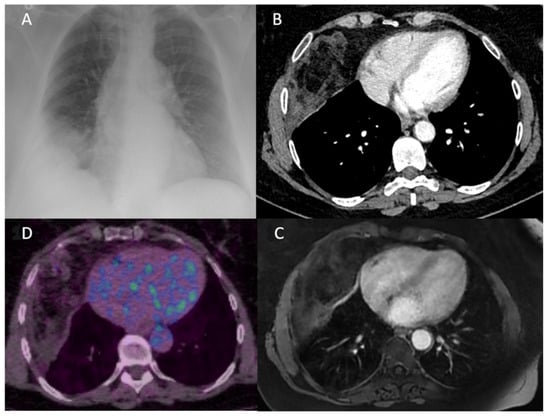

A 54-year-old woman with a medical history of severe obesity, myocardial infarction, hypertension and resection of uterine fibroids presented with an epigastric and right sub costal pain that had been progressing for 1 year. Physical examination did not reveal much information except a pain on peri-umbilical palpation. She had no nicotine or alcohol-dependent behavior. Vital signs were within normal values. Laboratory tests did not show any infectious syndrome. The electrocardiogram did not reveal any anomaly. The abdominal ultrasound revealed gallstones and a chest X-ray, routinely performed, showed an opacity in the right costo-phrenic angle (Figure 1A). Thus, a complement of investigation was performed with a thoraco-abdominopelvic CT scan. The CT scan showed a heterogeneous pleural mass, with a fatty and tissue component, without calcification and not appearing to invade neighboring structures or the chest wall (Figure 1B). Chest MRI was then performed to better understand the nature of this lesion. The MRI confirmed a heterogeneous mass with both fatty and tissue components of antero-inferior right subpleural location, without arguments for adjacent organ or chest wall invasion, but whose appearance remains suggestive of a liposarcoma (Figure 1C). An 18-fluorodeoxyglucose positron-emission tomography scan showed a low hypermetabolism of the lesion with a standardized uptake value of 1.8 (Figure 1D). No other FDG uptake was observed.

Figure 1. (A) Chest X-ray showing a non-systematized opacity of the right costo-diaphragmatic angle making the diagnosis between pleural effusion and thoracic mass difficult. (B) CT scan of the chest (axial view) confirming the presence of a heterogeneous intra thoracic mass not appearing to be in the lung parenchyma. (C) An axial T1-weighted MR image of the chest identifying a tumorous chest wall mass with both fat and tissue components, suggestive of liposarcoma. (D) 18-fluorodeoxyglucose (FDG) positron emission tomography showing a low hypermetabolism of this lesion with a standardized uptake value of 1.8.